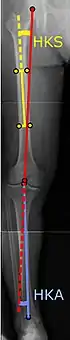

![]() |

Angles commonly measured before knee replacement surgery: |

To indicate knee replacement in case of osteoarthritis, its radiographic classification and severity of symptoms should both be substantial. Such radiography should consist of weightbearing X-rays of both knees- AP, Lateral, and 30 degrees of flexion. AP and lateral views may not show joint space narrowing, but the 30 degree flexion view is most sensitive for narrowing. Full length projections are also used in order to adjust the prosthesis to provide a neutral angle for the distal lower extremity. Two angles used for this purpose are:

- Hip-knee-shaft angle (HKS),[8] an angle formed between a line through the longitudinal axis of the femoral shaft and its mechanical axis, which is a line from the center of the femoral head to the intercondylar notch of the distal femur.[10]

- Hip-knee-ankle angle (HKA),[9] which is an angle between the femoral mechanical axis and the center of the ankle joint.[10] It is normally between 1.0° and 1.5° of varus in adults.[11]